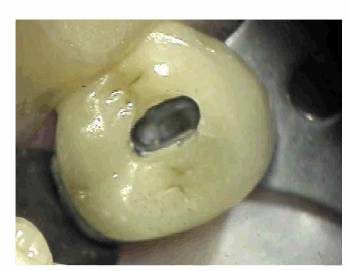

pulp is still vital. The mini-tip, when used in conjunction with a prepared

test cavity or a small opening in a cast crown (Figures 19-16A, and 19-16B), is quite advantageous. This tip

Figure 19-16A: Access through porcelain and metal to the dentin.

Figure 19-16B: Mini-tip placed on dentin through prepared cavity.